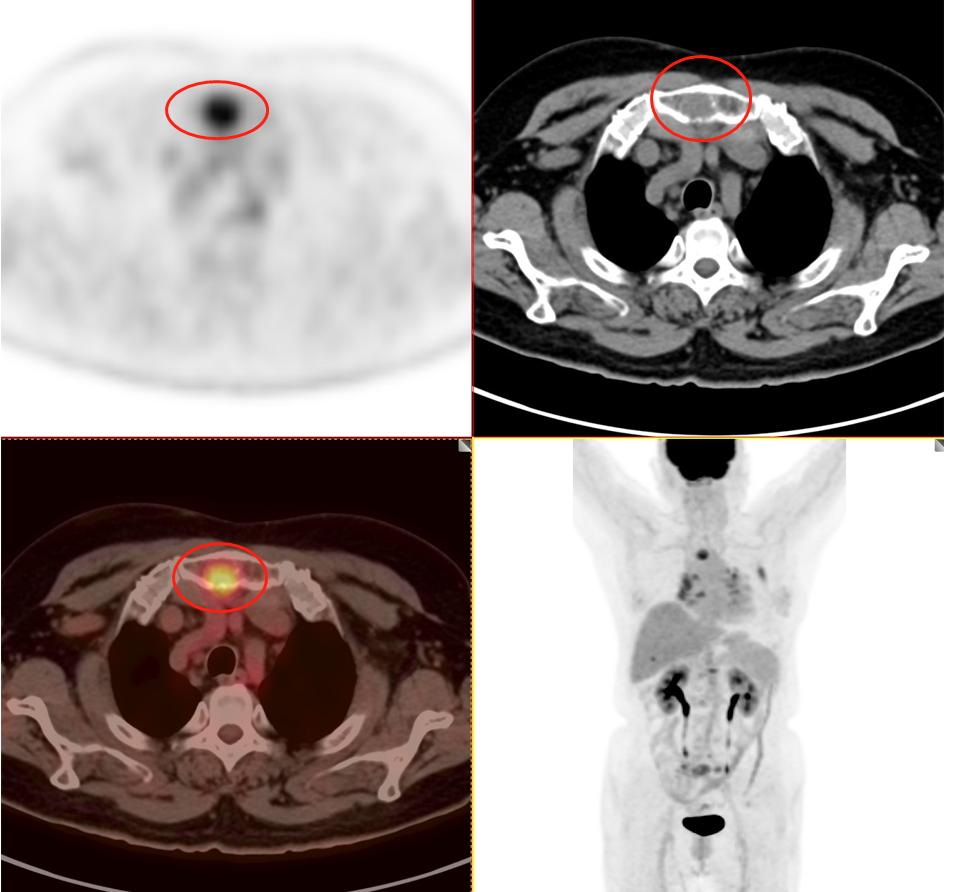

患者2:图5

患者2:图6

图4-5分别提示:胸骨、腰椎、骶骨及右侧髂骨骨转移。

因此该患者的肿瘤分期与第一位患者截然不同,同样病灶都在3cm以内,该患者属于T1cN3M1c 属于ⅣB期 最晚一期。这例患者当然不能手术了,只有寄希望于基因检测,如果有匹配的靶向药物,结合全身化疗或者免疫治疗,有一部分人还是有不错的效果。